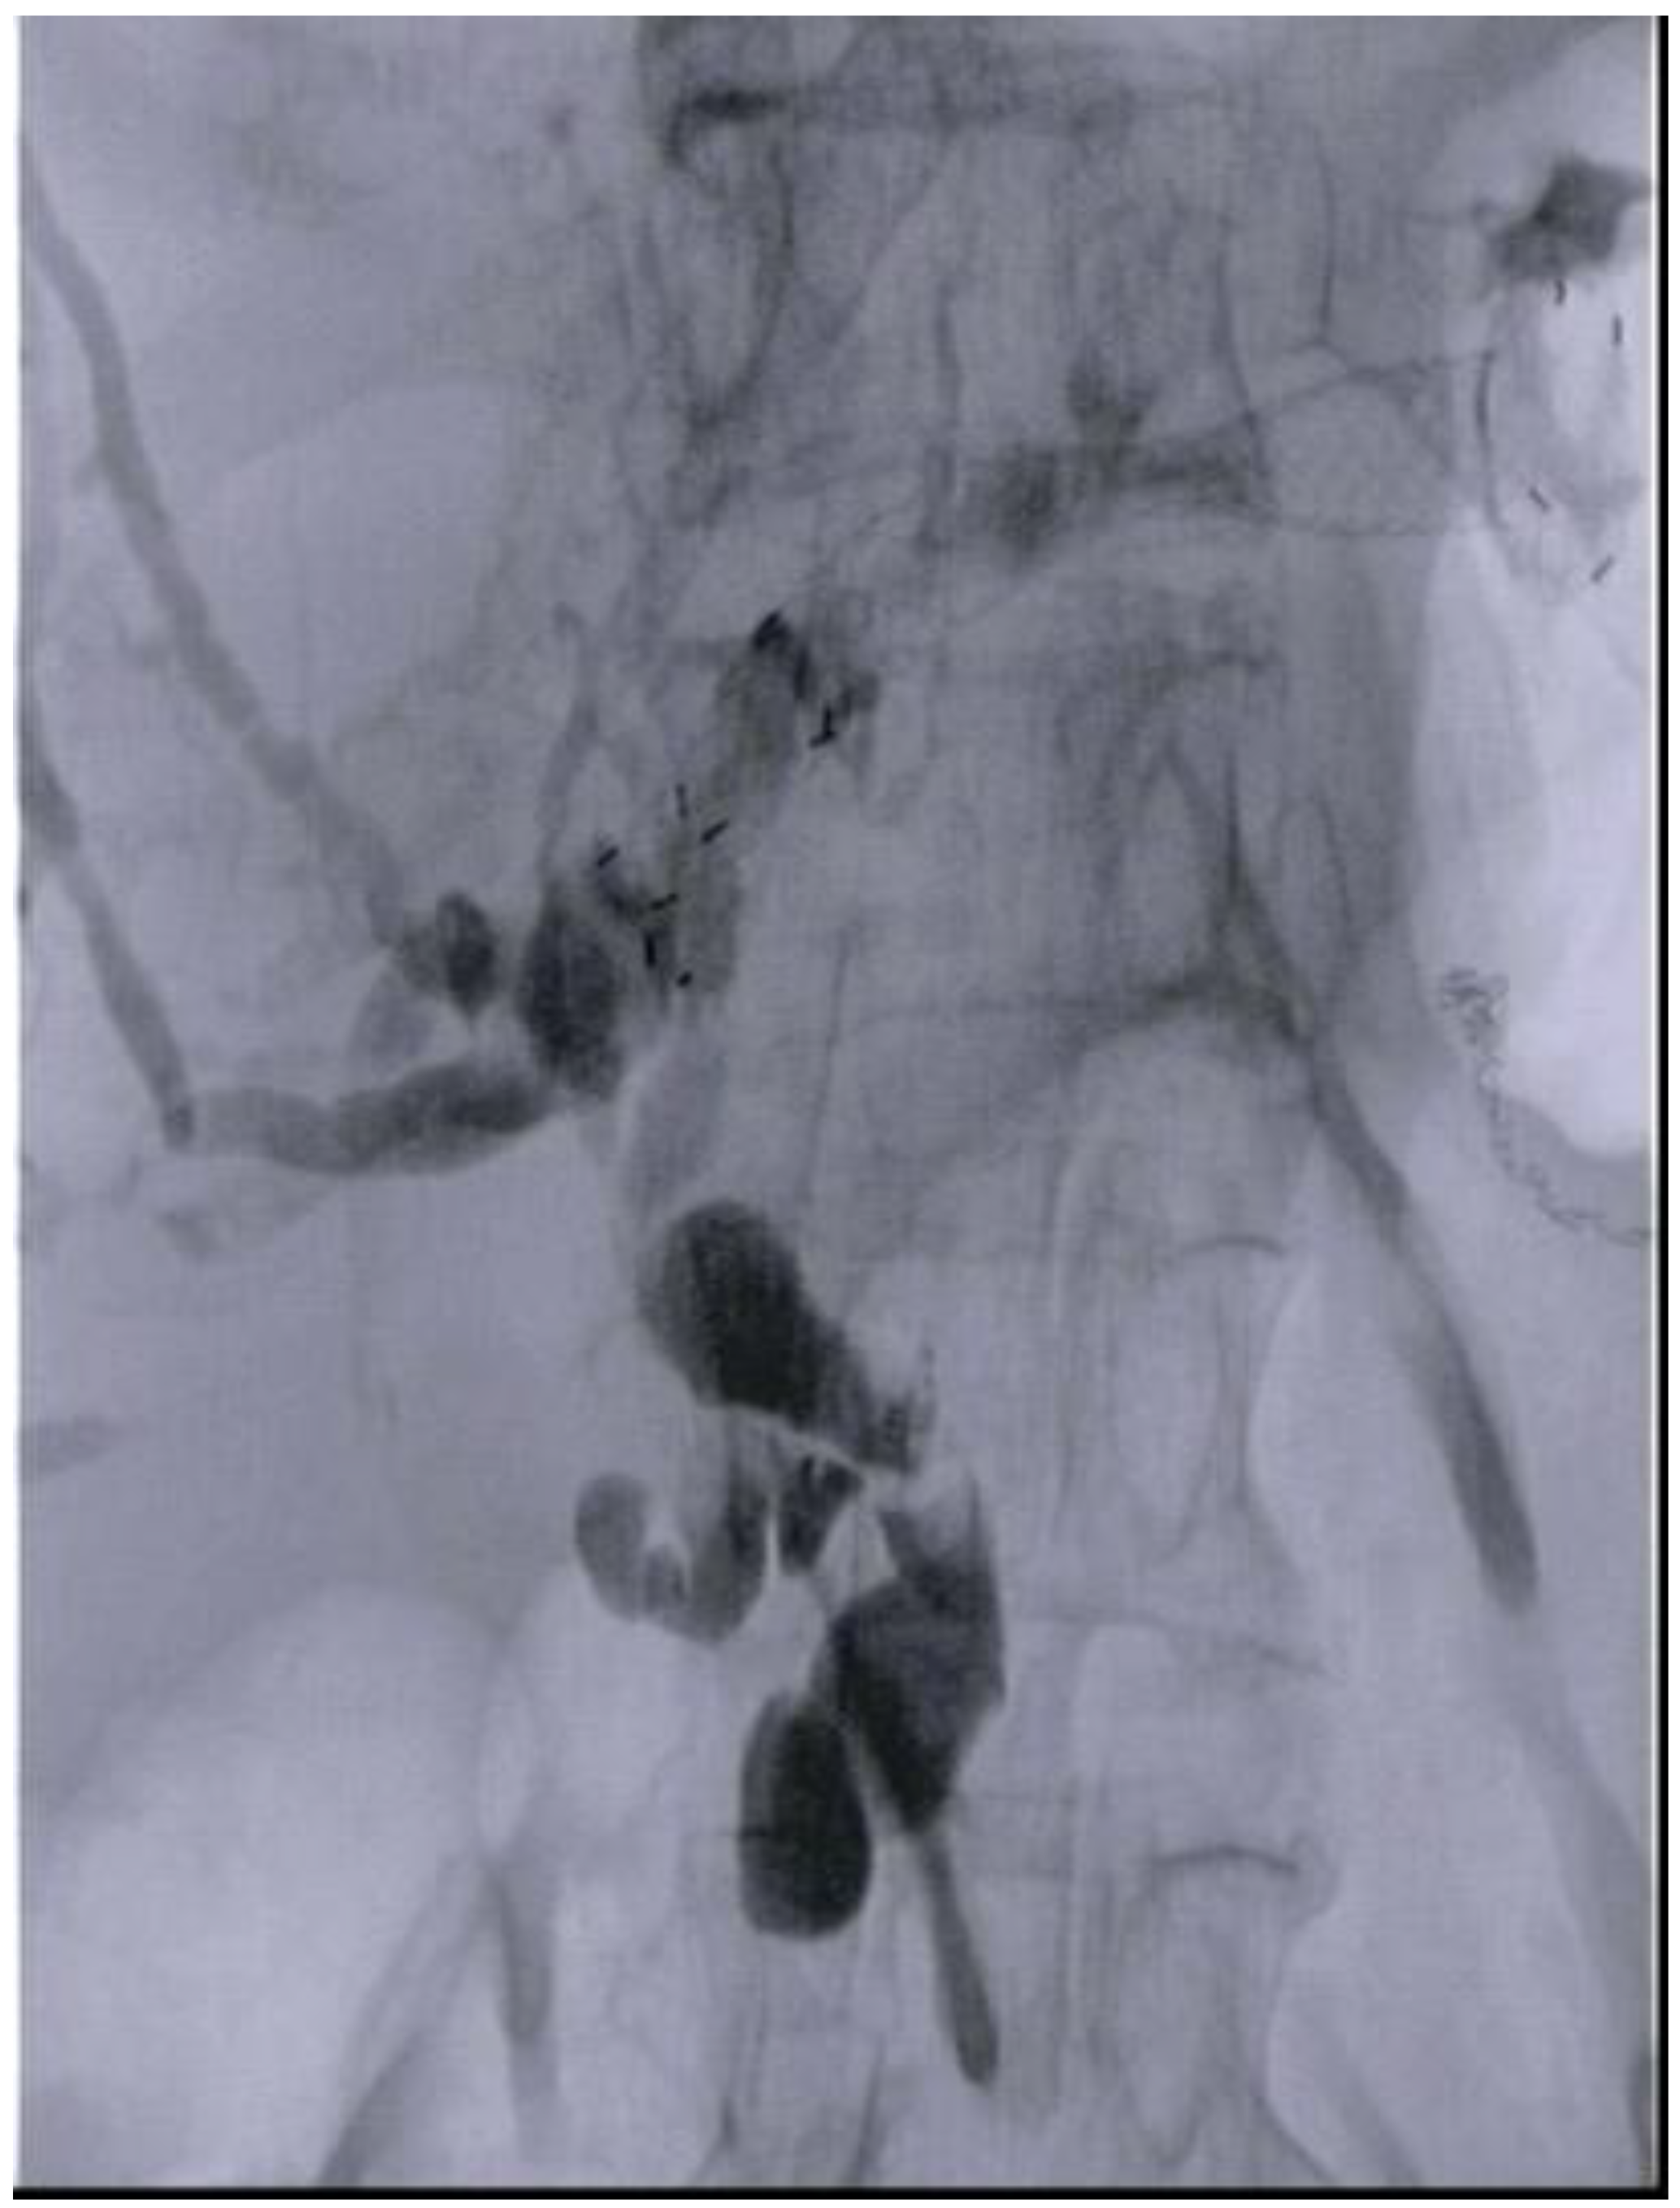

- Anderloni, A.; Fugazza, A.; Spadaccini, M.; Colombo, M.; Capogreco, A.; Carrara, S.; Maselli, R.; Ferrara, E.C.; Galtieri, P.A.; Pellegatta, G.; et al. Feasibility and safety of a new dedicated biliary stent for EUS-guided hepaticogastrostomy: The FIT study (with video). Endosc. Ultrasound 2023, 12, 59–63. [Google Scholar] [CrossRef] [PubMed]

- Ogura, T.; Kitano, M.; Takenaka, M.; Okuda, A.; Minaga, K.; Yamao, K.; Yamashita, Y.; Hatamaru, K.; Noguchi, C.; Gotoh, Y.; et al. Multicenter prospective evaluation study of endoscopic ultrasound-guided hepaticogastrostomy combined with antegrade stenting (with video). Dig. Endosc. 2018, 30, 252–259. [Google Scholar] [CrossRef] [PubMed]

- Fugazza, A.; Colombo, M.; Spadaccini, M.; Vespa, E.; Gabbiadini, R.; Capogreco, A.; Repici, A.; Anderloni, A. Relief of jaundice in malignant biliary obstruction: When should we consider endoscopic ultrasonography-guided hepaticogastrostomy as an option? Hepatobiliary Pancreat. Dis. Int. 2022, 21, 234–240. [Google Scholar] [CrossRef]

- Cho, J.H.; Park, S.W.; Kim, E.J.; Park, C.H.; Park, D.H.; Lee, K.J.; Lee, S.S. Long-term outcomes and predictors of adverse events of EUS-guided hepatico-gastrostomy for malignant biliary obstruction: Multicenter, retrospective study. Surg. Endosc. 2022, 36, 8950–8958. [Google Scholar] [CrossRef]